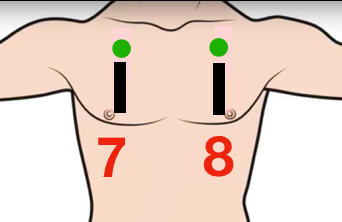

Poumons Antérieurs (S)

Glissement du poumon = pas de pneumothorax

Pneumothorax